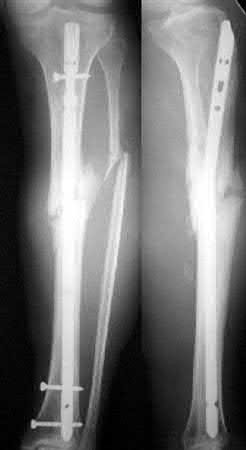

What is the most common type of malalignment after intramedullary nailing of distal 1/3 extra-articular tibia fractures using a infrapatellar approach when compared with plating?

The most common type of malalignment after intramedullary nailing of distal 1/3 extra-articular tibia fractures using an infrapatellar approach when compared with plating is valgus malalignment.

Fixation of distal one-third tibial shaft fractures can be successfully treated with either intramedullary nailing or plating. The literature describes advantages and disadvantages to both approaches, however intramedullary nailing has been shown to lead to increased rates of valgus malunion. Recent studies have shown that using a suprapatellar approach may decrease the incidence of valgus malalignement.

Vallier et al performed a randomized prospective study to compare plate and nail stabilization for distal tibia shaft fractures by assessing complications and secondary procedures. One-hundred and four patients were randomized to either reamed intramedullary nailing, or medial distal tibia plate fixation.

Primary angular malalignment was identified in 17 patients (16.3%). This included four patients treated with tibial plating (8.3%) and 13 patients treated with nails (23%, P = 0.02). Eight of these (7.7% of all patients) had malalignment between 6° and 10° of angulation. Valgus was the most common

angular deformity, accounting for 70% of angular deformity cases.

Avilucea et al. looked at the immediate postoperative alignment of distal tibia fractures (within 5 cm of the tibial plafond) treated with suprapatellar intramedullary nail (IMN) insertion compared with the infrapatellar technique. They found primary angular malalignment of ≥5 degrees occurred in 35 (26.1%) patients with infrapatellar IMN insertion and in 5 (3.8%) patients who underwent suprapatellar IMN insertion. They conclude suprapatellar IMN technique results in a significantly lower rate of malalignment compared with the infrapatellar IMN technique.